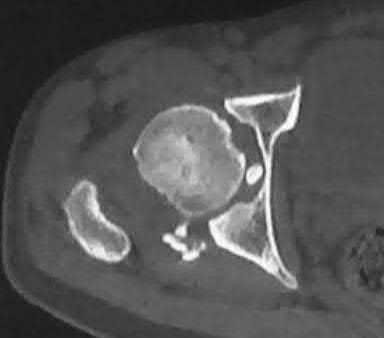

A 15-year-old boy presents with a permeative lytic lesion in the femoral diaphysis with aggressive periosteal reaction ('onion skinning'). Biopsy reveals uniform small round blue cells. Cytogenetic analysis of this tumor will most likely demonstrate which of the following translocations?

Explanation

The clinical and radiographic description is classic for Ewing sarcoma. The characteristic cytogenetic abnormality is a balanced translocation t(11;22)(q24;q12), which fuses the EWS gene on chromosome 22 with the FLI1 gene on chromosome 11. This is seen in approximately 85-90% of Ewing sarcomas. t(9;22) is the Philadelphia chromosome (CML), t(X;18) is seen in synovial sarcoma, t(2;13) in alveolar rhabdomyosarcoma, and t(12;16) in myxoid liposarcoma.